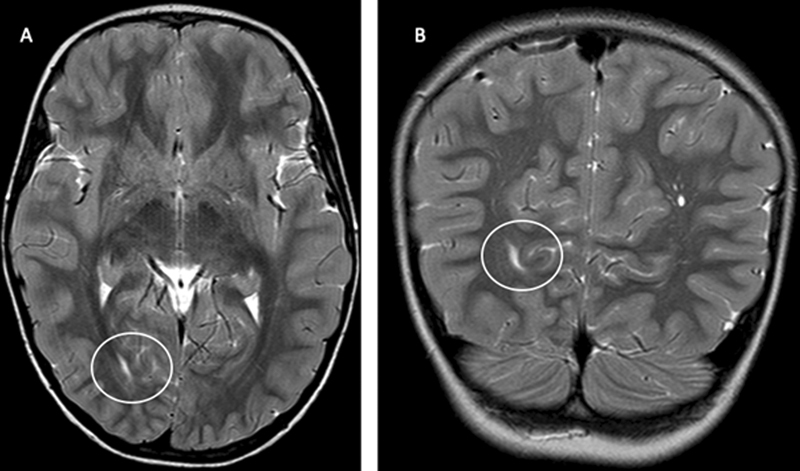

Abstract Image